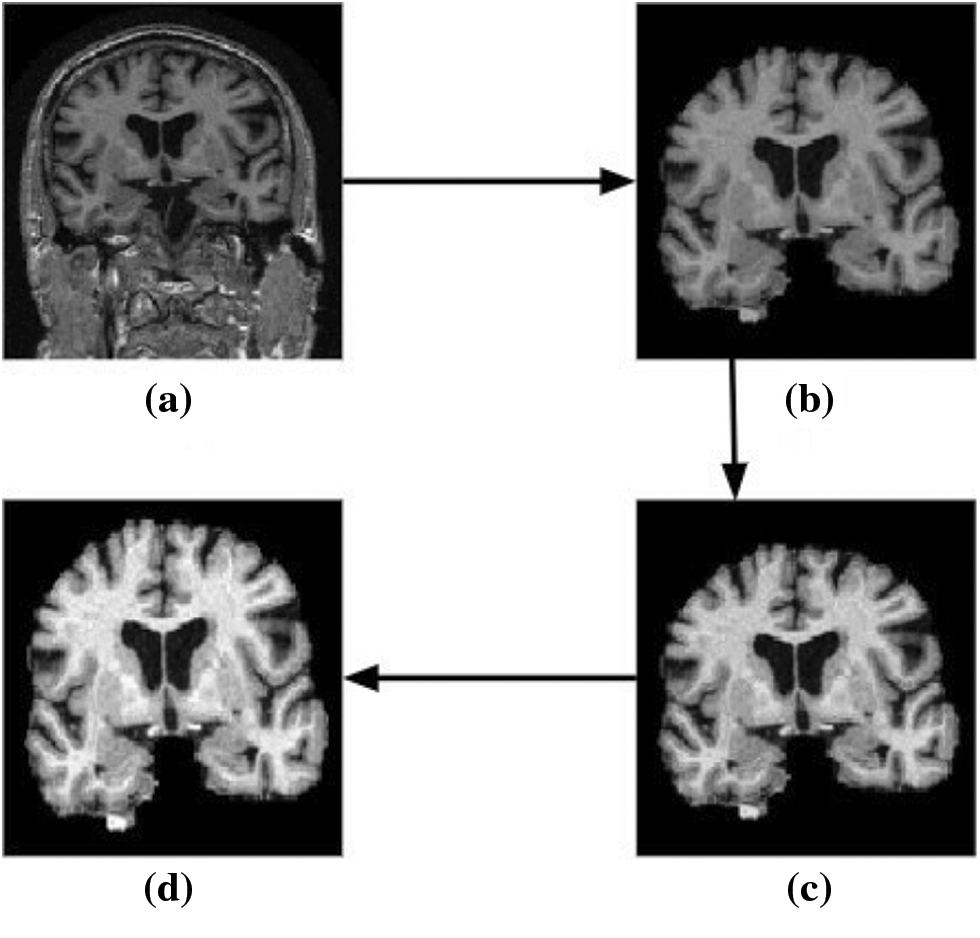

The results obtained for the proposed model employing 3D CNN are discussed in this section. The filtered image volumes obtained from the ADNI data set are again passed through various pre-processing stages, namely skull stripping, bias field correction, and intensity normalization. The two-dimensional view of the result after each pre-processing phase is shown in Fig. 10. The final 3D scan obtained after the various pre-processing stages is given as input to the proposed classification model.

Figure 10: Two-dimensional view of the results obtained for various pre-processing stages using brain MRI scans as input. (a) Input image (b) skull stripped image (c) bias field corrected output, and (d) image obtained after intensity normalization